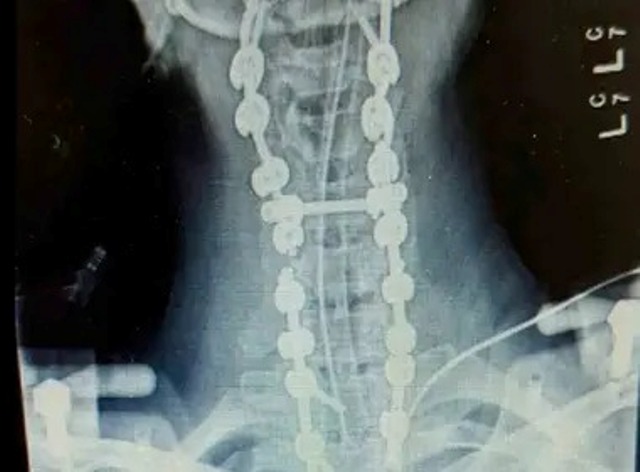

Megan fue operada de emergencia y así los médicos lograron fusionar el cráneo a la columna vertebral y logró sobrevivir a la terrible decapitación, que, de acuerdo con estadísticas, tiene una tasa de mortalidad del 90% debido a la probabilidad de que las señales nerviosas entre el cerebro y el cuerpo se dañen, lo que provoca parálisis en órganos vitales como los pulmones y el corazón.

Hasta el momento, la mujer lleva un total de 37 cirugías desde su accidente, dejando su cuerpo fusionado desde el cráneo hasta la pelvis y su cabeza incapaz de moverse en ninguna dirección.